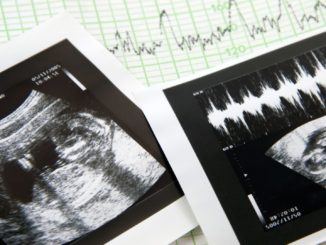

Medizinethikerin sieht Schwangerschaftsabbrüche als Dilemma

Aus Sicht der Medizinethikerin Christiane Woopen handelt es sich beim Thema Schwangerschaftsabbrüche um ein Dilemma, aus dem es keinen konfliktfreien Ausweg gibt. „Es geht zum einen um die Selbstbestimmung, die Gesundheit und das Leben der […]